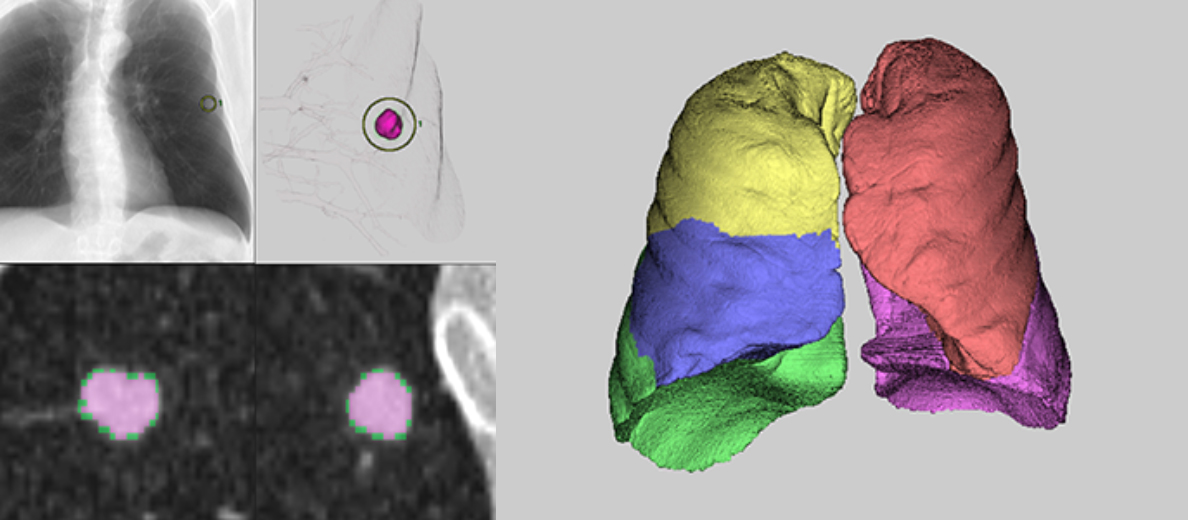

Ứng dụng phân tích các nốt mờ phổi theo thời gian, cũng như các vùng phế quản và suy giảm thấp của phổi. Có thể tách các thùy phổi tự động hoặc thủ công.

Ứng dụng trích xuất phổi, động mạch phổi, tĩnh mạch phổi, phế quản và các vùng khác để hiển thị hình ảnh 3D của phổi. Mô phỏng cắt bỏ phổi có thể được thực hiện bằng cách trích xuất và khoanh vùng các vùng lãnh thổ của mạch phổi và phế quản, điều này hữu ích cho việc lập kế hoạch tiền phẫu.

Úng dụng xác định ba đường dẫn tối ưu dẫn đến tổn thương phổi. Mô phỏng ống soi phế quản được thực hiện dọc theo đường đi, giúp nhìn rõ các thủ thuật khó khăn trước khi thực hiện thăm khám xâm lấn.